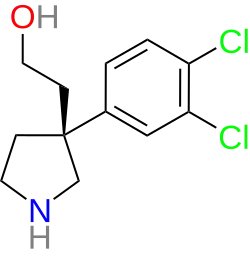

- Liming Shao (Sepracor/Sunovion). 3’,4’-Dichlorotramadol,[132] CID:53321058 (S/N/D = 19/04/01 nM).[133][134]